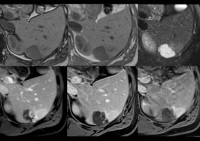

MRI of the liver.

МРТ печени. Метод неинвазивного визуального обследования печени и желчевыводящих путей, основанный на изменении полярности атомов водорода в организме под воздействием радиоволн и постоянного магнитного поля. Используется для получения информации о однородности и плотности паренхимы печени, а также для исследования сосудов и желчных протоков. МРТ печени используется для диагностики объемных образований различной природы, воспалительных процессов, атрофии, структурных изменений. Методика используется для подтверждения аномалий развития, наличия камней и оценки общего состояния организма. Проводится амбулаторно или в стационаре с внутривенным контрастированием. Требуется самостоятельная подготовка к экзамену в течение двух дней.

Магнитно-резонансная томография печени использовалась в клинической медицине с конца прошлого века, но не относится к рутинным диагностическим методам из-за ее высокой стоимости. Сканирование отличается точностью полученных данных благодаря снимкам отдельных срезов с минимальным расстоянием между ними. На основании полученных результатов также возможно построить трехмерную модель. В связи с этим магнитно-резонансная томография печени обычно назначается после скрининга диагностических процедур (УЗИ печени и желчного пузыря) для уточнения и дополнения результатов. Это имеет практическое значение в гастроэнтерологии, хирургии и онкологии.